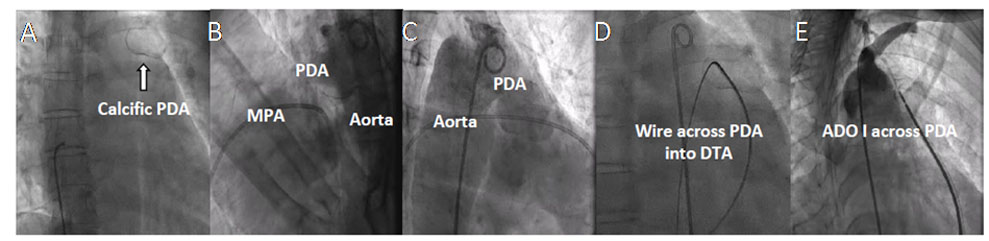

The management options were discussed in the combined meeting involving cardiac surgeons, radiologists, and cardiologists, and with the family before deciding to proceed for transcatheter closure using an Amplatzer Duct Occluder (ADO I) (Abbott). (Figure 2). The procedure was done under local anesthesia (Videos 1-6). An arch injection using a 5-French (Fr) diagnostic pigtail angiography catheter (Cordis) was obtained to define the anatomy of the PDA in the lateral and right anterior oblique views. As the PA end measured 8 mm, it was decided to use a 12/10 ADO I device to close the defect. The PDA was crossed from the PA end using a 0.035-inch, double-length, Amplatz Super Stiff guidewire (Boston Scientific), which was exchanged for a double-length stiff wire. Over the stiff wire, using an 8-Fr delivery system, the 12/10 ADO I device was deployed under echocardiographic and fluoroscopic guidance. The device was released after confirming the position with a check angiogram and an echocardiographic assessment. The patient was discharged after 24 hours and found symptomatically improved at 12 months of follow-up.